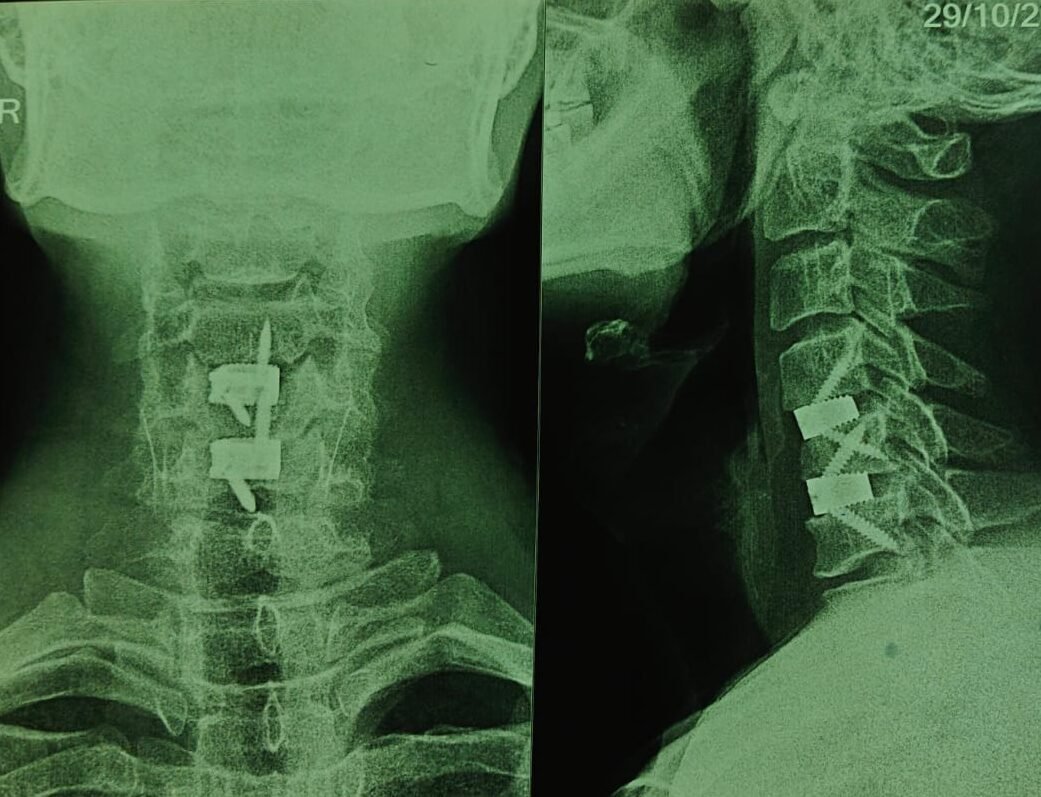

2️⃣ Fusion (Stabilization)

- A spacer (bone graft or cage) is placed in the disc space

- The vertebrae are stabilized using a plate and screws

- Over time, the bones fuse into a single solid unit

- Fusion monitoring: Follow-up X-rays are done to assess bone healing and implant position.